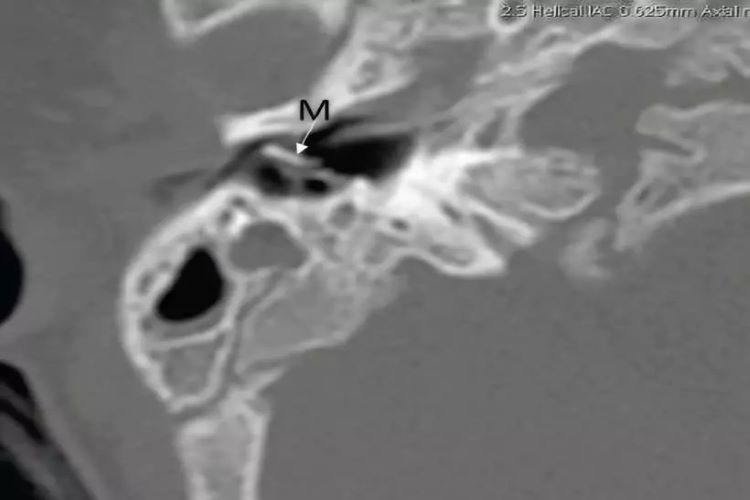

先天性内耳畸形

大前庭导水管综合征主要表现为听力波动性下降,个别患者会表现为突发性耳聋,也有患者表现为发作性眩晕伴波动性听力下降。不完全分隔Ⅱ型主要表现为患耳重度听力障碍或全聋,听性脑干反应不能引出,若伴前庭功能障碍则出现眩晕等症状,影像检查可见发育异常,存在缺如。